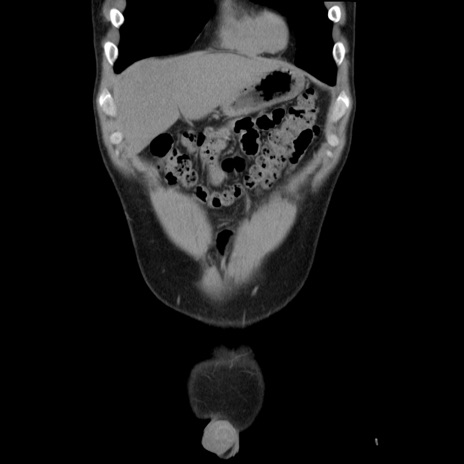

症例36(冠状断像)

【症例】20歳代 男性

【主訴】心窩部痛

【現病歴】今朝より上腹部痛あり。一旦軽快していたが再度出現したため救急要請。昨日夕に白身の魚を含む刺身を食べた。

【身体所見】BP 136/89mmHg、HR 74/min、BT 37.0℃、腹部:膨満、軟、心窩部に圧痛あり。反跳痛なし、筋性防御なし、腸雑音やや亢進あり。

【データ】WBC 17700、CRP 0.48